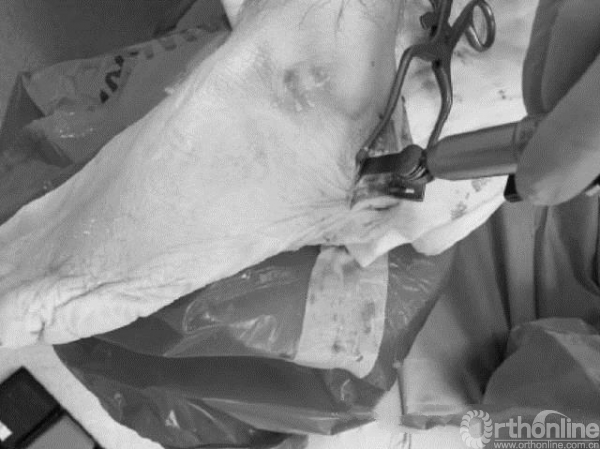

选定安全区后,在此区域内截骨。传统的开放手术使用摆锯截骨(图A),经皮术则要使用高速低扭矩磨钻(图B)。

图 A

图 B